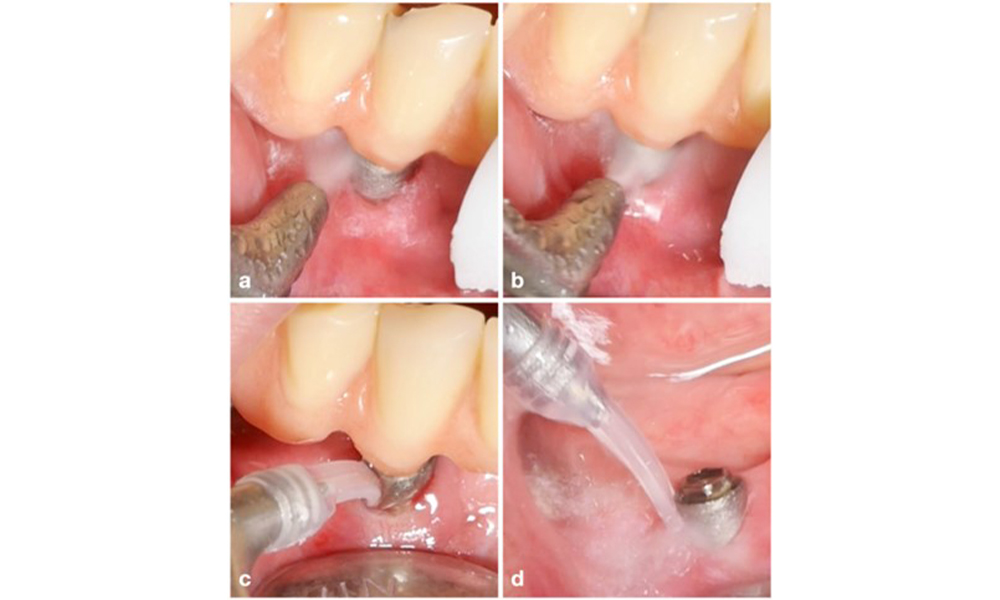

Die Wahl der Mittel hängt von den klinischen Gegebenheiten wie zum Beispiel Zahnstein im Unterschied zu weichen Belägen ab. Bei Zahnstein sollten als Erstes Titan- bzw. Kunststoffküretten oder Ultraschallscaler mit speziell geformter Spitze zum Einsatz kommen, gefolgt von einem Luftpoliergerät (Abb. 7). Bei ausschließlich weichen Belägen ist ein Luftpoliergerät allein unter Umständen ausreichend. Luftpoliergeräte sind bediener- und patientenfreundlich und mindestens so wirksam wie Standardinstrumente (Schwarz et al. 2015a).

Patientenfall mit periimplantärer Mukositis, mangelnder Oralhygiene und Zahnstein (a). In einem solchen Fall ist eine Kombination unterschiedlicher Geräte ratsam. Beispielsweise sind Ultraschallscaler mit speziell geformter Spitze zum Entfernen des Zahnsteins erforderlich (b), während der restliche weiche Biofilm mit einem Luftpoliergerät entfernt werden kann (c-d).

Abb. 7. Patientenfall mit periimplantärer Mukositis, mangelnder Oralhygiene und Zahnstein (a). In einem solchen Fall ist eine Kombination unterschiedlicher Geräte ratsam. Beispielsweise sind Ultraschallscaler mit speziell geformter Spitze zum Entfernen des Zahnsteins erforderlich (b), während der restliche weiche Biofilm mit einem Luftpoliergerät entfernt werden kann (c-d).

Das Management einer Periimplantitis bei als therapierbar eingestuften Implantaten besteht aus einer nicht-chirurgischen Phase, oftmals gefolgt von einer chirurgischen Intervention. Bei den nicht-chirurgischen Verfahren kommen ähnliche Maßnahmen zum Einsatz wie bei der Behandlung einer periimplantären Mukositis. Laborexperimente lassen darauf schließen, dass Luftpoliergeräte mit subgingivaler Düse bei der Biofilmentfernung im Vergleich zu Hand- oder Ultraschallinstrumenten allem Anschein nach bestimmte Vorteile bieten (Herrera et al. 2023; Moharrami et al. 2019; Ronay et al. 2017) (Abb. 9).

Patientenfall mit Periimplantitis. Die nicht-chirurgische Behandlung erfolgt mit dem supragingivalen (a-b) und subgingivalen Handstück eines Luftpoliergeräts (c-d). Durch Abnehmen der Suprakonstruktion lässt sich ein besserer Zugang zur Implantatoberfläche erzielen (d).

Abb. 9. Patientenfall mit Periimplantitis. Die nicht-chirurgische Behandlung erfolgt mit dem supragingivalen (a-b) und subgingivalen Handstück eines Luftpoliergeräts (c-d). Durch Abnehmen der Suprakonstruktion lässt sich ein besserer Zugang zur Implantatoberfläche erzielen (d).